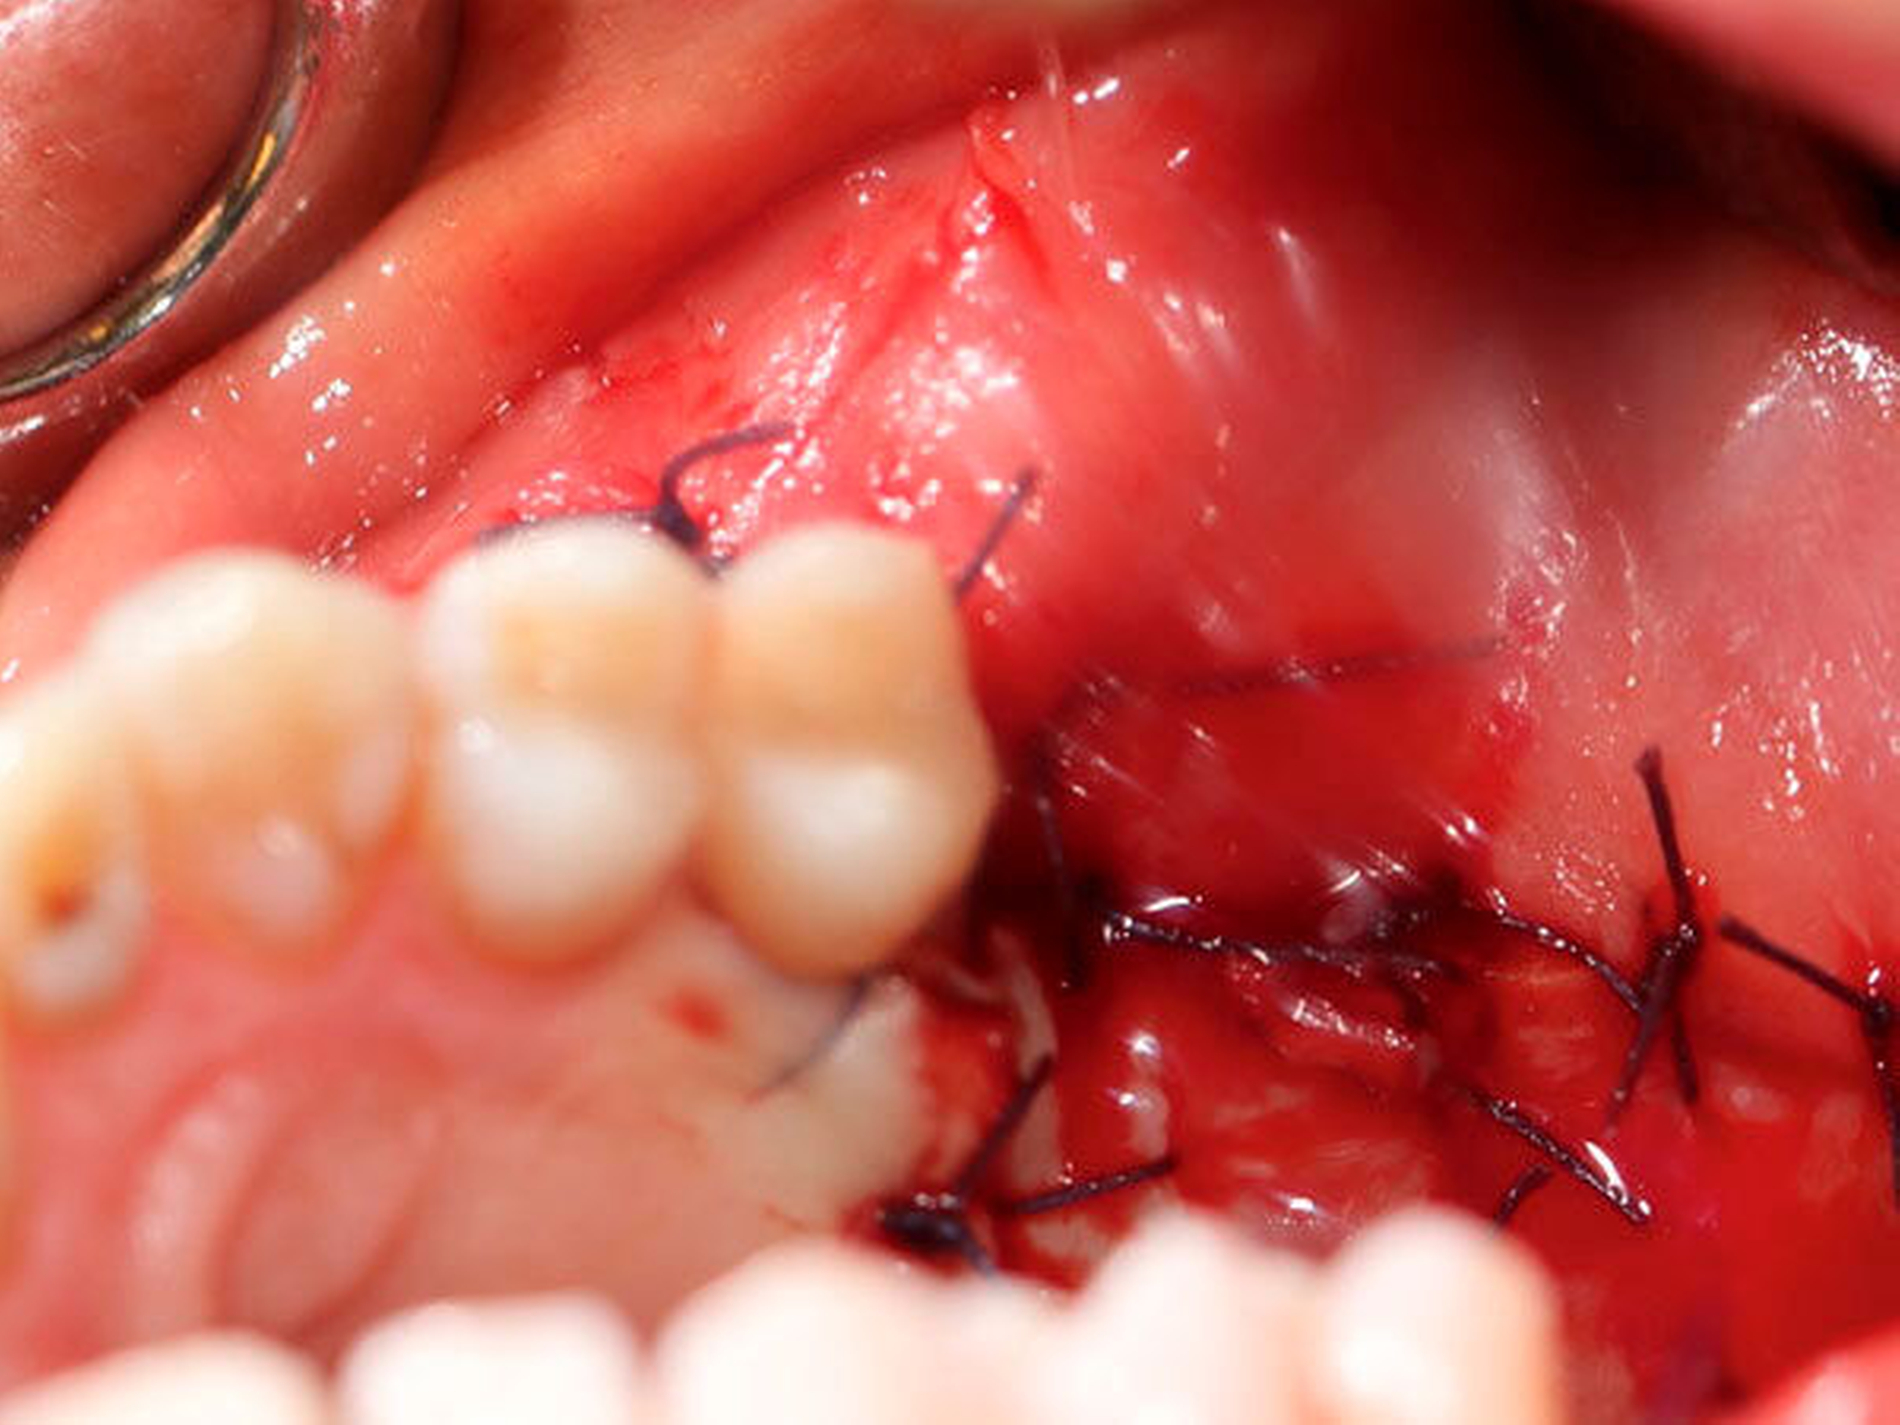

Die Allgemein- und Familienanamnese der Patientin war bis auf eine medikamentös eingestellte Hypothyreose unauffällig. Extraoral bestand kein auffälliger Befund, insbesondere keine Druckdolenz oder Nervdefizit über der Kieferhöhle links. In Regio 27 zeigte sich eine Mund-Antrum-Verbindung nach frustranem Deckungsversuch, aus der sich seröse Flüssigkeit entleerte (Abbildung 2). Der Zahn 26 reagierte negativ auf Perkussion und war avital. Nach sorgfältiger Aufklärung erfolgte die Resektion des Befunds in Intubationsnarkose. Folgend auf die Extraktion des Zahnes 26 (Abbildung 3) wurde eine Kastenresektion der linken Maxilla von distal des Zahnes 25 bis in den Tuberbereich bei makroskopischem Einhalten eines Sicherheitsabstands von 0,5 cm durchgeführt. Das narbig anmutende Gewebe in der Kieferhöhle wurde ausgeschält und en bloc mit dem Oberkieferresektat entfernt (Abbildung 4). Der Knochen wurde hier belassen, da er klinisch und radiologisch nicht infiltriert war.

Der Defekt wurde mit einer lokalen Lappenplastik gedeckt (Abbildung 5), eine vorab angefertigte Verbandsplatte zum Wundschutz eingegliedert. Die abschließende histologische Auswertung (Abbildung 6) bestätigte, dass es sich bei dem kompletten Resektat um das bereits ex domo vor-diagnostizierte, teils plexiforme Ameloblastom handelte. Aufgrund der Größe des Tumors erfolgte ein Staging mittels CT-Thorax und Abdomen, das jedoch keinen Nachweis einer Metastasierung erbrachte. Bei mikroskopisch knappen Sicherheitsabständen nach palatinal sowie an der Nasenscheidewand und zur Orbita hin wurde die Patientin über ein differenzial-therapeutisches Vorgehen mit radikal-chirurgischem Vorgehen versus engmaschige klinische und radiologische Nachkontrollen aufgeklärt. Die Patientin entschied sich nach eingehender Aufklärung für die engmaschigen Nachkontrollen. Eine ossäre Rekonstruktion (Abbildung 7) wird derzeit von der Patientin nicht gewünscht.